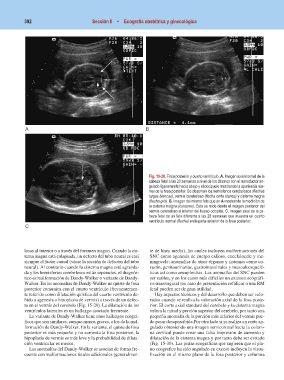

Fig. 15-28. Fosa posterior y cuarto ventrículo. A. Imagen axial normal de la

cabeza fetal a las 20 semanas a nivel de los tálamos con el transductor an-

gulado ligeramente hacia abajo y el occipucio mostrando la apariencia nor-

mal de la fosa posterior. Se observan los hemisferios cerebelosos (flechas

largas blancas), vermis cerebeloso (flecha corta blanca) y cisterna magna

(flecha gris). B. Imagen del mismo feto que en A mostrando la medición de

la cisterna magna (cursores). Ésta se mide desde el margen posterior del

vermis cerebeloso al interior del hueso occipital. C. Imagen axial de la ca-

beza fetal de un feto diferente a las 28 semanas que muestra un cuarto

ventrículo normal (flecha) en la parte anterior de la fosa posterior.